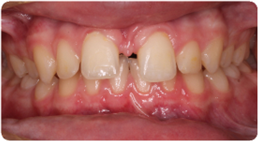

Each case shows the front view and an arch or side view, before and after BioLign Method-guided treatment.

All cases treated within 6–12 months.

Crowding with irregular gaps resolved into even alignment